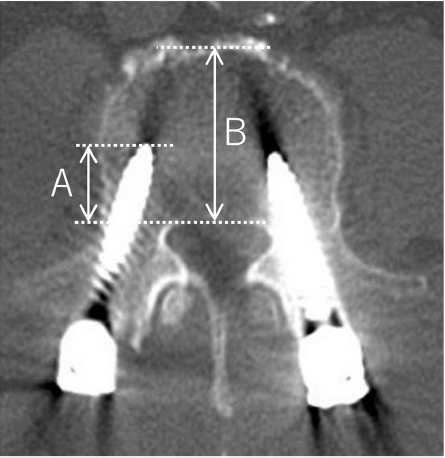

螺钉椎体置入深度比(%)的测量方法:A/B*100%

ROC曲线分析确定60.0%的粗细适配度和54.2%的螺钉椎体置入深度比是实现骨融合的最佳截止值(cutoff值)。